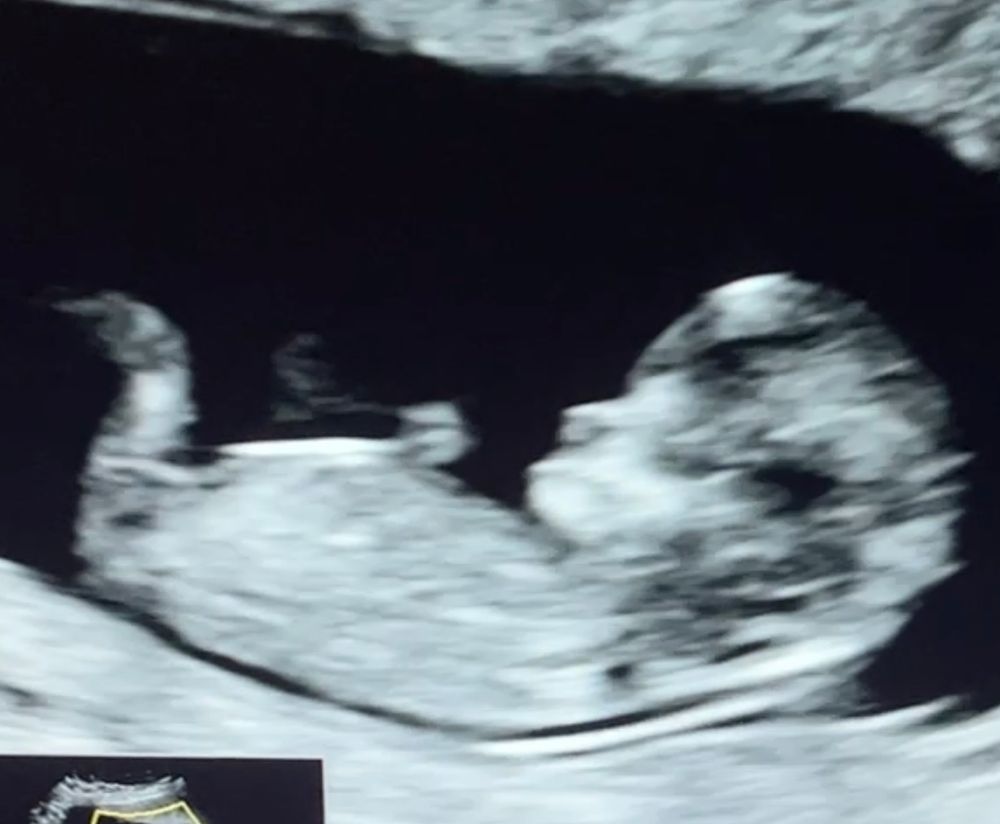

На втором фото похоже на девочку

Кактусеныш, второе фото это вчерашнее узи, врач тоже предположила девочку, говорит на мальчика не похожа лялька. А на узи неделю назад увидели что-то между ножек, но фото не дали( в 12 недель тоже девочку предположили

Блин, у вас как у меня. А мне прогнозируют девочку. Я за девочку. Я столько этих Бугорков за несколько дней пересмотрела тут.😁